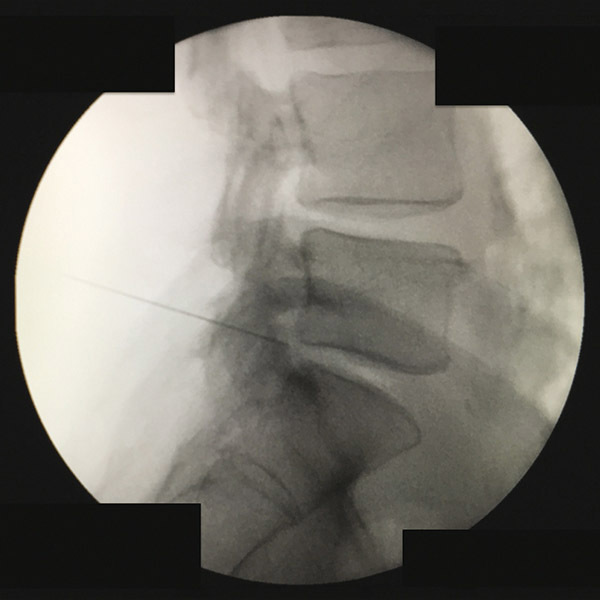

Abord foraminal L5-S1 sous fluoroscopie

2. Abord foraminal L5-S1 sous fluoroscopie